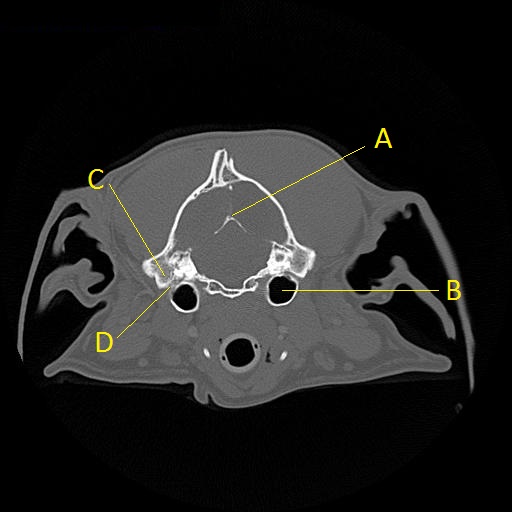

Q. Identify the structures labeled below:

A.

A. osteum tentorium cerebelli

B. tympanic bulla

C. mastoid process

D. stylomastoid foramen